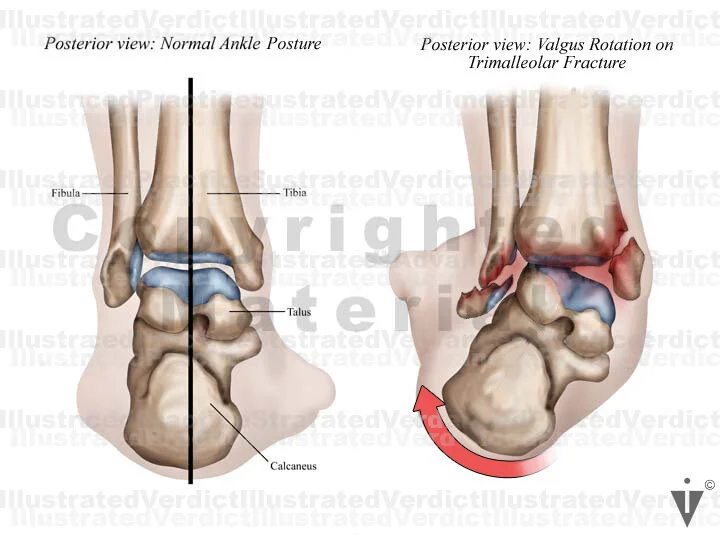

1. Normal posterior ankle: bony structures

2. Valgus rotation on trimalleolar fracture